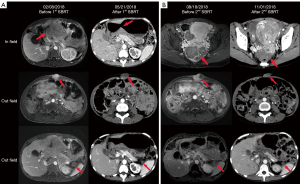

In March 2018, she received SBRT for the retroperitoneal mass with a total dose of 30Gy in 6 fractions, and 2 months later (May 21st, 2018) both the in-field and out-field tumors dramatically shrunk (Figure 5A). In August 2018, the follow-up CT scan revealed a new pelvic metastasis, then a subsequent SBRT (30 Gy/6 F) was given for the pelvic mass, and again 2 months later (November 1st, 2018) she achieved PR for both the in-field and out-field tumors (Figure 5B). However, after the second SBRT in January 2019, multiple new metastases were observed.